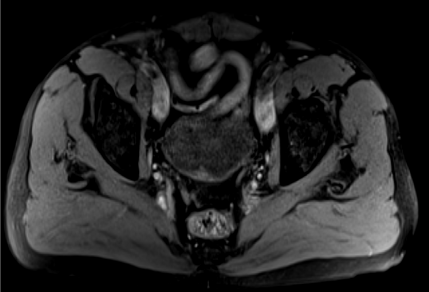

Follow-up flexible cystoscopy at 4months under local anaesthesia showed recurrence of the larger, incompletely resected 2cm bladder lesion (Figure 4). Subsequent CT scan with contrast showed a lesion on the right bladder wall. The abdominal organs showed no abnormality and there was no abdominal or pelvic lymphadenopathy (Figure 5). A Pelvic MRI showed an enhancing area of thickening on the right bladder wall with ill-defined peri-vesical fat in that area (Figure 6). The patient had a further cystoscopy and complete resection of the bladder lesion was achieved due to less inclusive calcification. Histology confirmed amyloid deposition, with apple-green birefringence, with extensive ossification and accompanying giant cell reaction and no evidence of malignancy. Immunochemical staining of amyloid deposits, using monospecific antibodies reactive with serum amyloid a protein (SAA), transthyretin (TTR) and Kappa and Lambda immunoglobulin chains was negative. Therefore, the conclusion was that the amyloid is of non-AA type. A further follow up with flexible cystoscopy under local anaesthesia every 6months showed no recurrence of the amyloid lesion in the bladder up to two years after the second resection (Figure 7).

Figure 7 Non-invasive bladder lesion on the right bladder wall on a contrast CT scan.